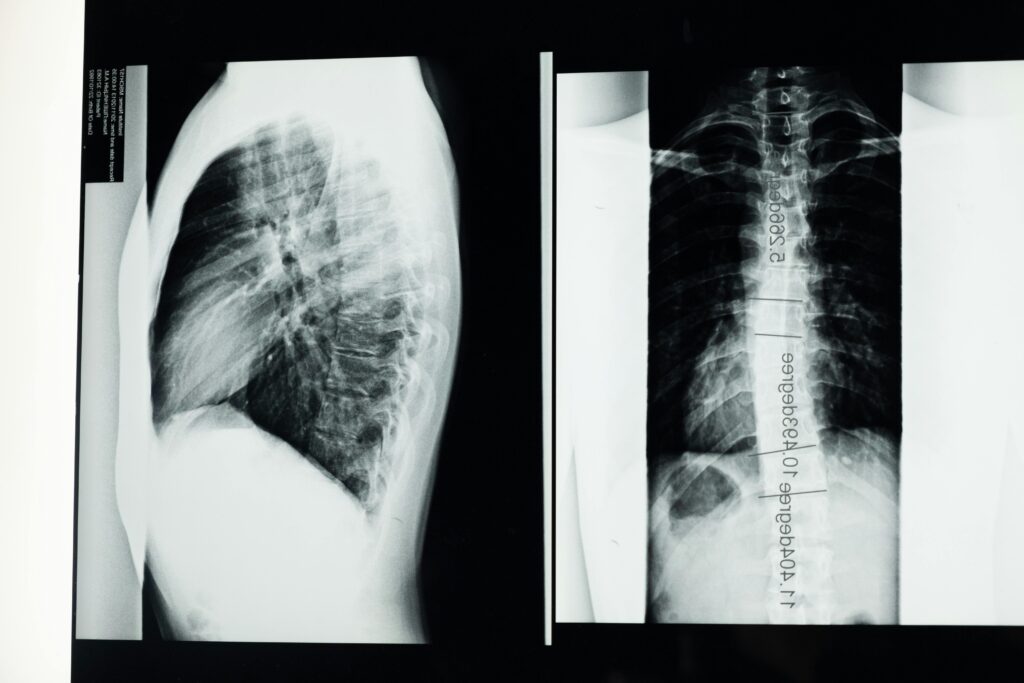

Recognizing the type and severity of a curve is crucial. Early intervention can significantly reduce the chance of progression and long-term complications. With proper imaging and assessment, practitioners can determine the best strategy for managing the condition at any stage.

Many Vancouver residents are seeking alternatives that support natural function and long-term spinal health. Chiropractic care is gaining recognition as an effective approach that targets both the skeletal structure and surrounding musculature. At Aquarius Chiropractic, we begin with a detailed posture analysis and imaging to assess spinal alignment and identify the direction of the curve, or convexity.